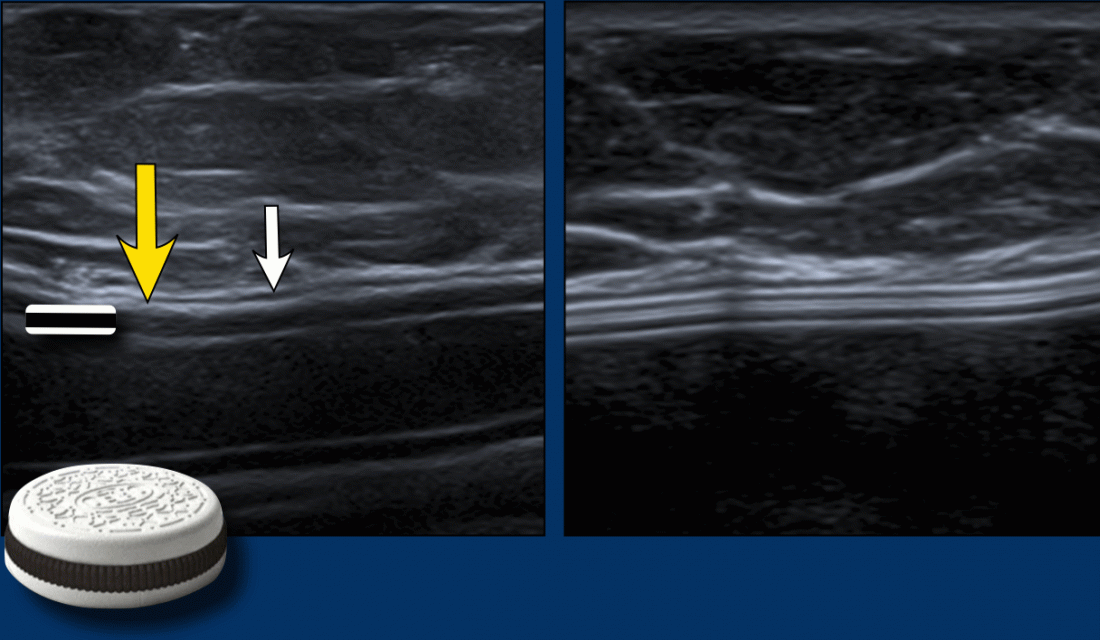

Breast Ultrasound Breast Implant Shell vs Fibrous Capsule (Sonography Capsule Breast Implant capsular contracture is a breast augmentation complication that develops when internal scar tissue forms. There are different ways a a capsulectomy is a surgical procedure to remove the capsule, the layer of thickened scar tissue, from around a breast implant. after breast augmentation surgery, it’s normal for your body to form a capsule around the implants composed. Capsule Breast Implant.